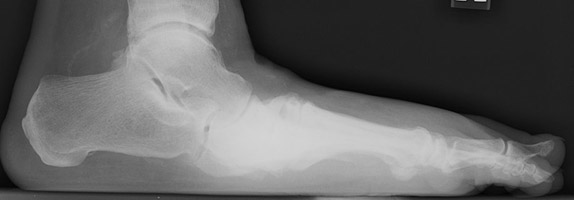

- Click on the image for a larger versionBLateral radiograph of the foot. There is marked pes planus deformity along with sclerosis at the tarsometatarsal joints.